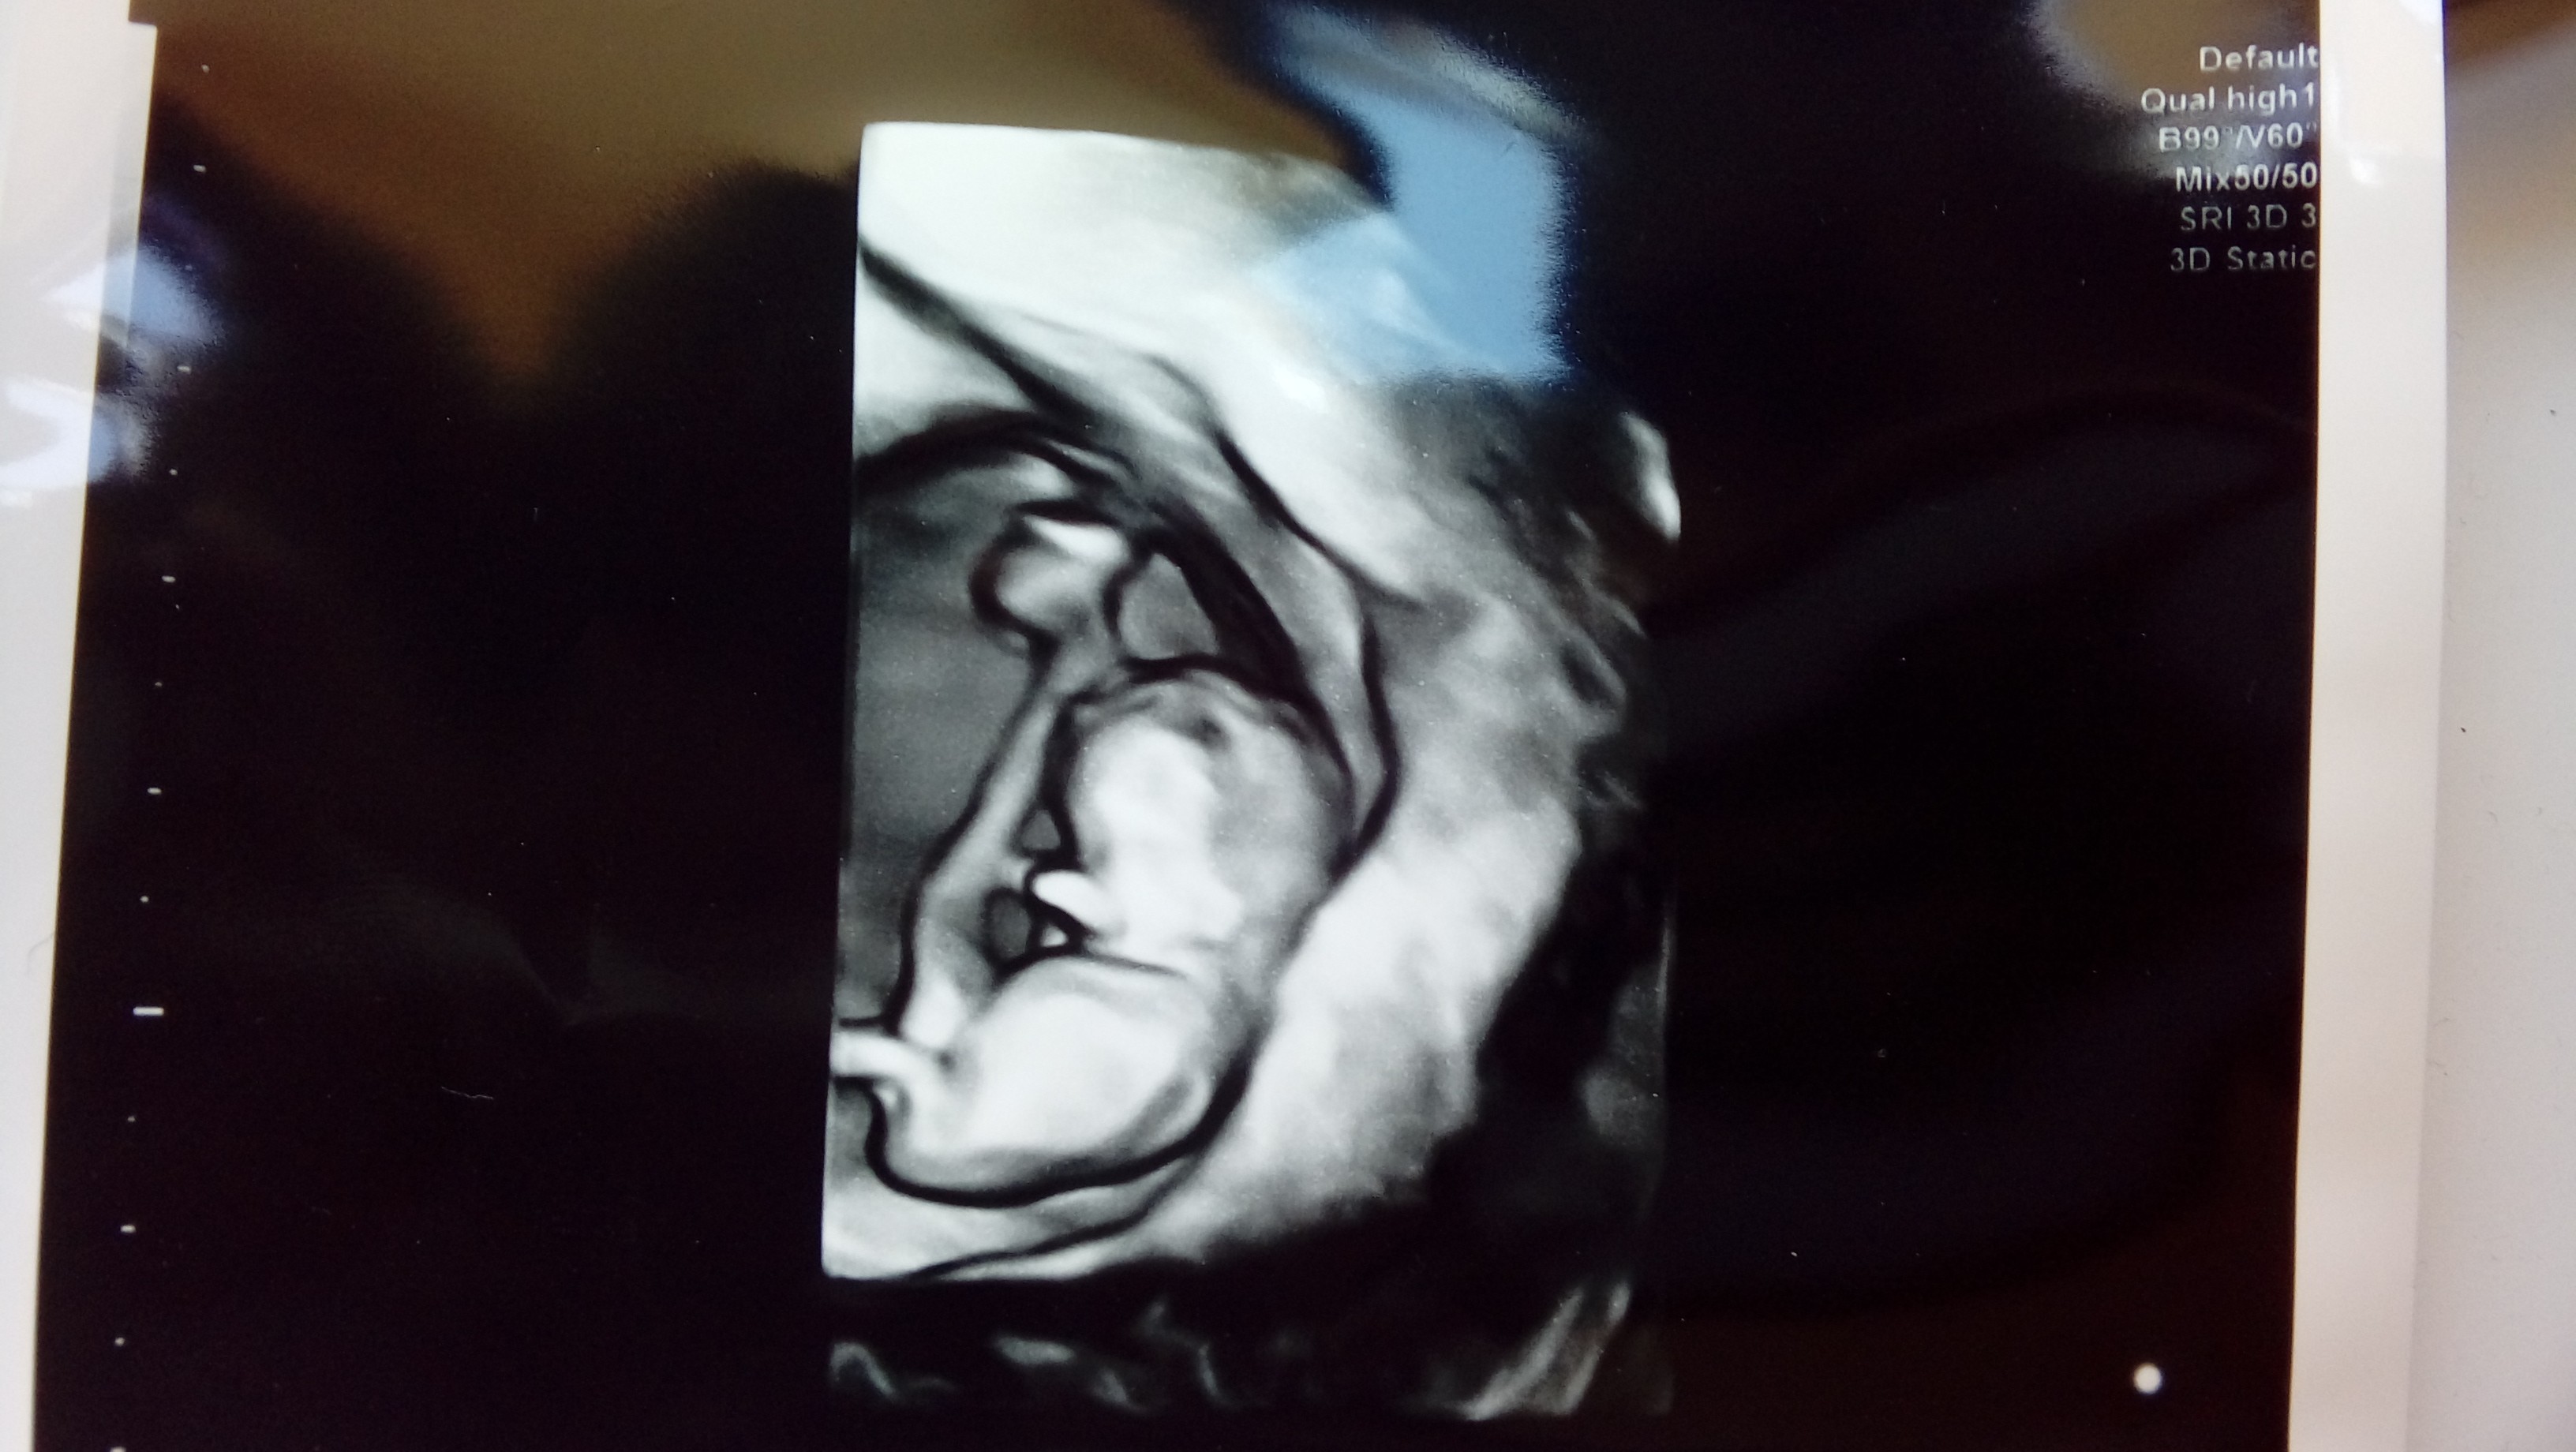

Ostatnia wizyta 8 maja i takie 3 cm bąbelka , kolejne prenatalne z testem pappa 25.05. Stresssss

• 20180508_131256.jpg

20180508_131256.jpg

649,1 KB · Wyświetleń: 149